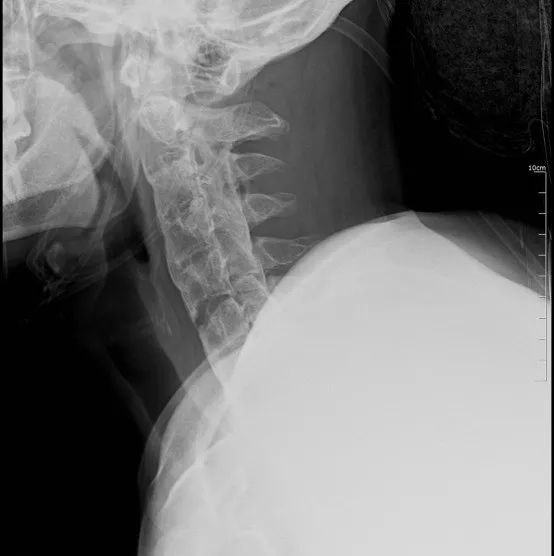

颈椎CT检查确认,患者颈椎曲度变直,符合强直性脊柱炎改变;颈C5-6对位欠佳,颈C6椎体及双侧上关节突有骨折可能。颈部核磁检查确认,患者颈C6椎体压缩性骨折,颈C6椎体上关节突骨折,颈C5椎体骨挫伤,颈段椎旁软组织损伤。

综合查体和影像学检查,患者以“颈椎骨折(C5/6)、强直性脊柱炎”收入我院,拟行手术治疗。